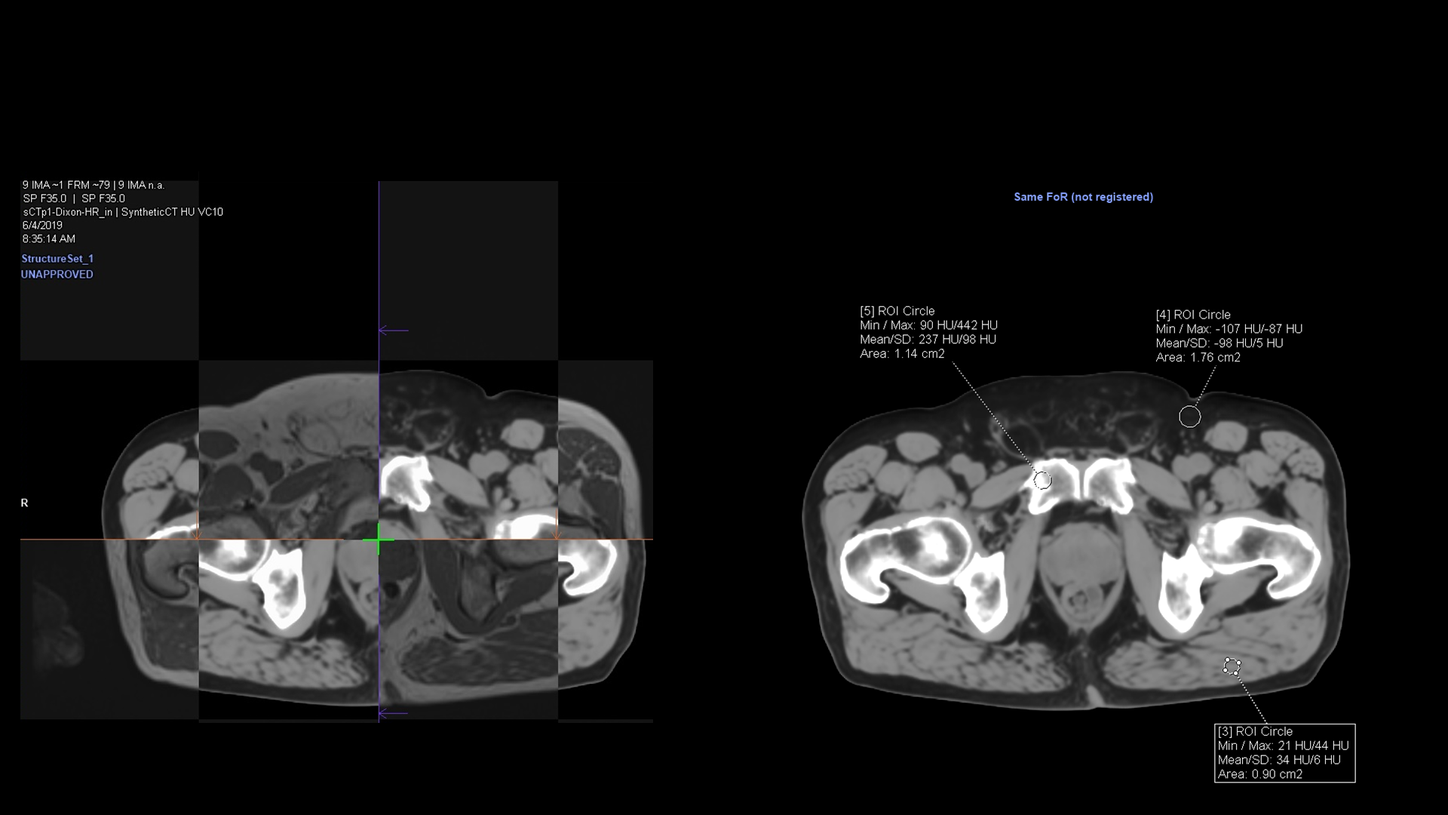

MR-based Synthetic CT offers the possibility of combining the superior soft-tissue contrast of MRI for organs-at-risk and target delineation with dosimetric planning. An MR-only workflow eliminates the need for CT to MRI registration, reducing systematic registration errors and unnecessary ionizing radiation from CT scans.

The data acquisition protocols for MR-based Synthetic CT are available with syngo MR XA11A and later software versions with RT Pro edition for MAGNETOM Sola and Vida, with syngo XA30 and later software Versions for MAGNETOM Aera and MAGNETOM Skyra.